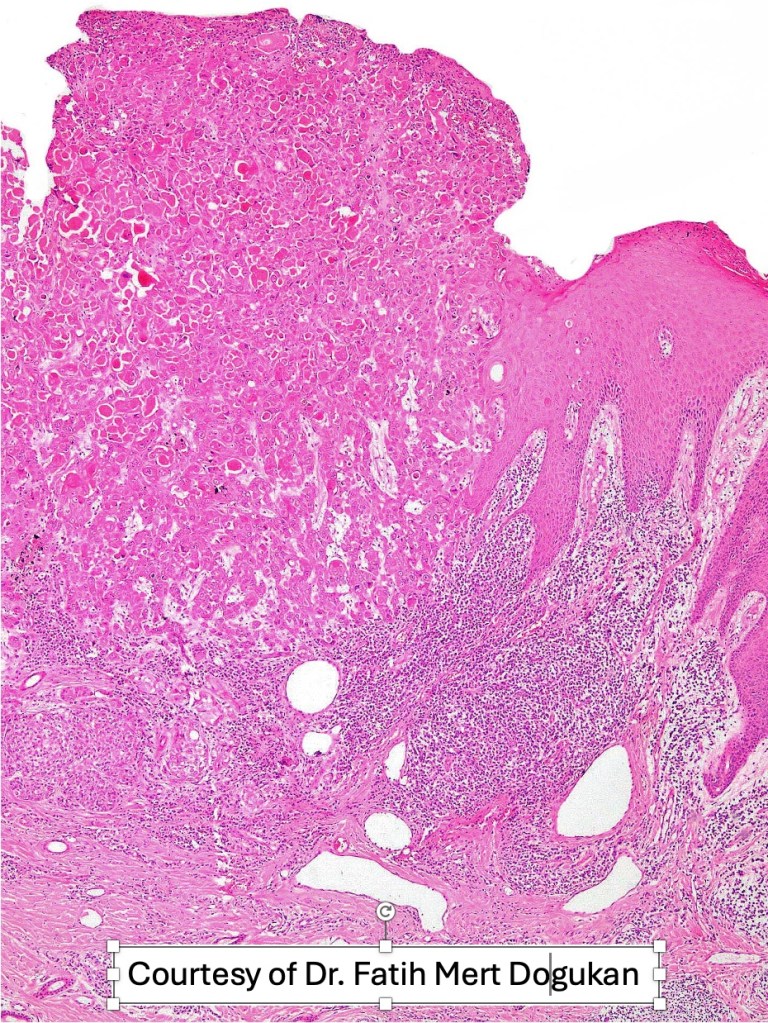

•Biphasic tumor

•Admixture of squamous carcinoma & pleomorphic spindled cell, osteoid, chondroid, MFH-like +/- osteoclast-like giant cells & rarely, smooth muscle, skeletal muscle, myofibroblastic or angiosarcomatous elements